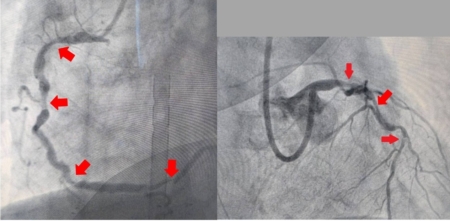

大千綜合醫院心臟內科醫師羅健賢表示,該位病人的心導管檢查顯示冠狀動脈左主幹與三條血管都嚴重狹窄,若要進行導管置放支架風險很高,因此建議接受風險較低的冠狀動脈繞道手術,但病人表示不願意。沒想到,病人接連併發急性肺水腫、急性腎衰竭,甚至心因性休克,因此緊急裝置葉克膜並進行複雜性心導管冠狀動脈整型術,以刀片氣球整型術切割血管壁上的斑塊,使血管更容易擴張,術中同時放置六支塗藥支架治療。病人術後第二天移除葉克膜,一週後脫離呼吸器、12天後轉入一般病房繼續藥物治療、血液透析,並進行床邊復健幫助體力恢復,終於在第28天順利出院返家。後續腎功能逐漸恢復,術後三個月已不需再洗腎。

由於複雜的冠狀動脈疾病,像是:多處血管狹窄或阻塞、血管分支複雜等,是無法透過單純的氣球擴張或支架植入來治療。因此,需要以複雜性心導管冠狀動脈整型術,也就是利用心導管搭配特殊技術(包含:刀片氣球整型術、冠狀動脈旋磨術、血管內震波氣球擴張術)來治療。此手術具有侵入性小、恢復快、提高治療效果等優點,但手術仍存在一定的風險,因此需要醫師更精細的手術技巧及術後專業的照護,才能有更高的成功率並降低手術風險。